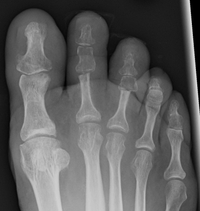

Krallenzehen nach der Operation

Je nach Ausdehnung des Befundes ist gelegentlich eine Fixierung der Zehe mittels Draht für 2-4 Wochen nötig; in dieser Zeit ist das Tragen eines Vorfußentlastungsschuhes sinnvoll. Der Draht kann danach problemlos und schmerzfrei entfernt werden. Nach Vollständiger Abheilung kann eine sportliche Aktivität wieder voll aufgenommen werden.